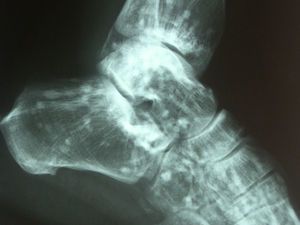

Diagnóstico y evoluciónEn la Rx que aportó la paciente se identificaron unos signos radiológicos que resultaron diagnósticos: numerosas imágenes radiopacas o esclerosas, pequeñas, homogéneas, bien definidas y circulares agrupadas en regiones periarticulares. Era un caso de osteopoiquilosis. No había manifestaciones clínicas con relación a esta enfermedad, tampoco se evidenciaron lesiones cutáneas. Se trataba de un hallazgo casual. A esta paciente se le solicitaron Rx de hombros, manos, pelvis, rodillas y pies (figs. 1–4), y se pudo comprobar que las lesiones halladas en el codo también estaban presentes en todas estas localizaciones. La osteopoiquilosis suele afectar a epífisis y metáfisis de huesos tubulares largos, carpo, tarso, pelvis y escápula de forma simétrica. El tamaño de las lesiones es uniforme.

DiscusiónLa osteopoiquilosis u osteopatía condensante diseminada es una displasia osteosclerótica asintomática. Su aparición antes de los 3 años es infrecuente, aparece tanto en varones como en mujeres. Existen casos hereditarios y esporádicos. Las manifestaciones clínicas suelen faltar, aunque en un 25% de casos pueden encontrarse lesiones cutáneas que consisten en infiltraciones fibrocolágenas, predisposición a la formación de queloides y lesiones similares a las de la esclerodermia. Los hallazgos radiológicos son diagnósticos1. El diagnóstico diferencial debe hacerse con metástasis osteoblásticas, mastocitosis y esclerosis tuberosa2. La distribución simétrica, la afectación de epífisis y metáfisis, y el tamaño uniforme de las lesiones son datos sugestivos de osteopoiquilosis. El aspecto normal de una gammagrafía ósea acabaría de apoyar el diagnóstico.